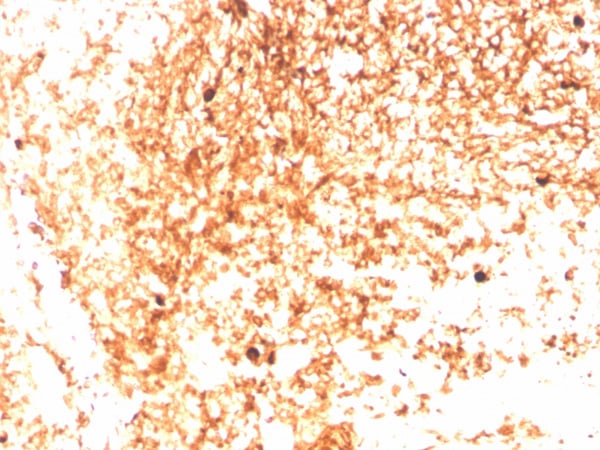

Recognizes a protein of 75kDa, identified as mu heavy chain of human immunoglobulins. It does not cross-react with alpha (IgA), gamma (IgG), epsilon (IgE), or delta (IgD), heavy chains, T-cells, monocytes, granulocytes, or erythrocytes. Monomeric IgM is expressed as a membrane bound antibody on the surface of B cells and as a pentamer when secreted by plasma cells. IgM antibody is prominent in early immune responses to most antigens. Aberrant levels are associated with immune deficiency states, hereditary deficiencies, myeloma, Waldenstrom's macroglobulinemia, chronic infection and hepatocellular disease. This MAb is useful in the identification of leukemias, plasmacytomas, and certain non-Hodgkin s lymphomas. The most common feature of these malignancies is the restricted expression of a single heavy chain class. Demonstration of clonality in lymphoid infiltrates indicates that the infiltrate is clonal and therefore malignant.

IHC (Immunohistochemistry)

Positive Control

293T, Raji or hPBL cells. Human tonsil or spleen (IHC).